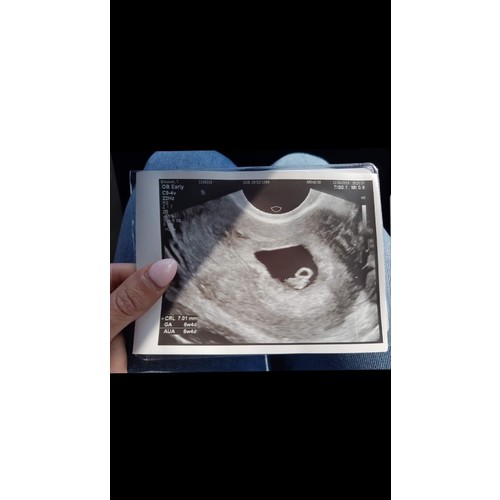

Dit was de allereerste echo

Met hoeveel weken was dit? Mooi echo 🥰

Dankje! Deze was met 5+5, nu ik ze zo even bij heb gepakt zie ik dat ik meer heb gehad dan ik dacht 🙈 ( dit ivm eerdere missed abortion ) ook nog met 6+4, 9+3 en toen de 12 weken echo. Zelf met 15 weken geslachts bepalende echo laten maken en toevallig vandaag de 20 weken echo gehad. 🎀💗